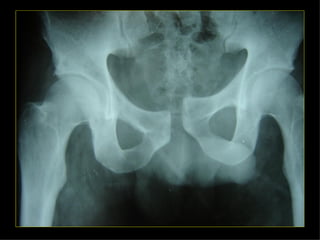

ESTABLES INESTABLES FxMalgaigne En libro abierto En asa de cubo En horcajadas Fx por avulsión Del ala iliaca Del sacro Fx aisladas de las ramas pélvicas

ESTABLES INESTABLES Fx Malgaigne En libro abierto En asa de cubo En horcajadas Fx por avulsión Del ala iliaca Del sacro Fx aisladas de las ramas pélvicas